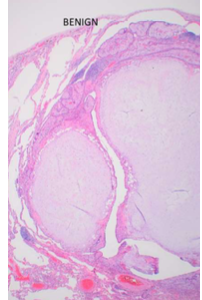

neoplastic tissue benign vs malignant

benign tumours